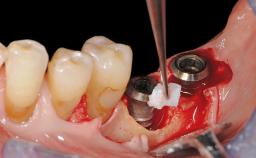

In this case, Myroslav Solonko, Ignacio Sanz Sánchez and Mariano Sanz present a treatment that aims to eliminate exposed implant threads by modifying the implant surface, converting a moderately-rough surface into a smooth surface.